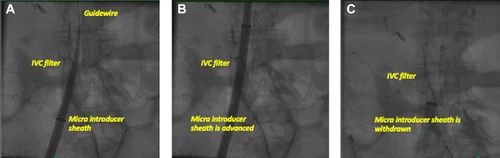

图3、输送鞘通过下腔静脉滤器

该患者有心动过缓、深静脉血栓形成病史,8月前下腔静脉放置了滤器(A,B) 。Micra输送鞘顺长导丝小心地推进。(C)在连续透视下仔细撤出Micra输送鞘。